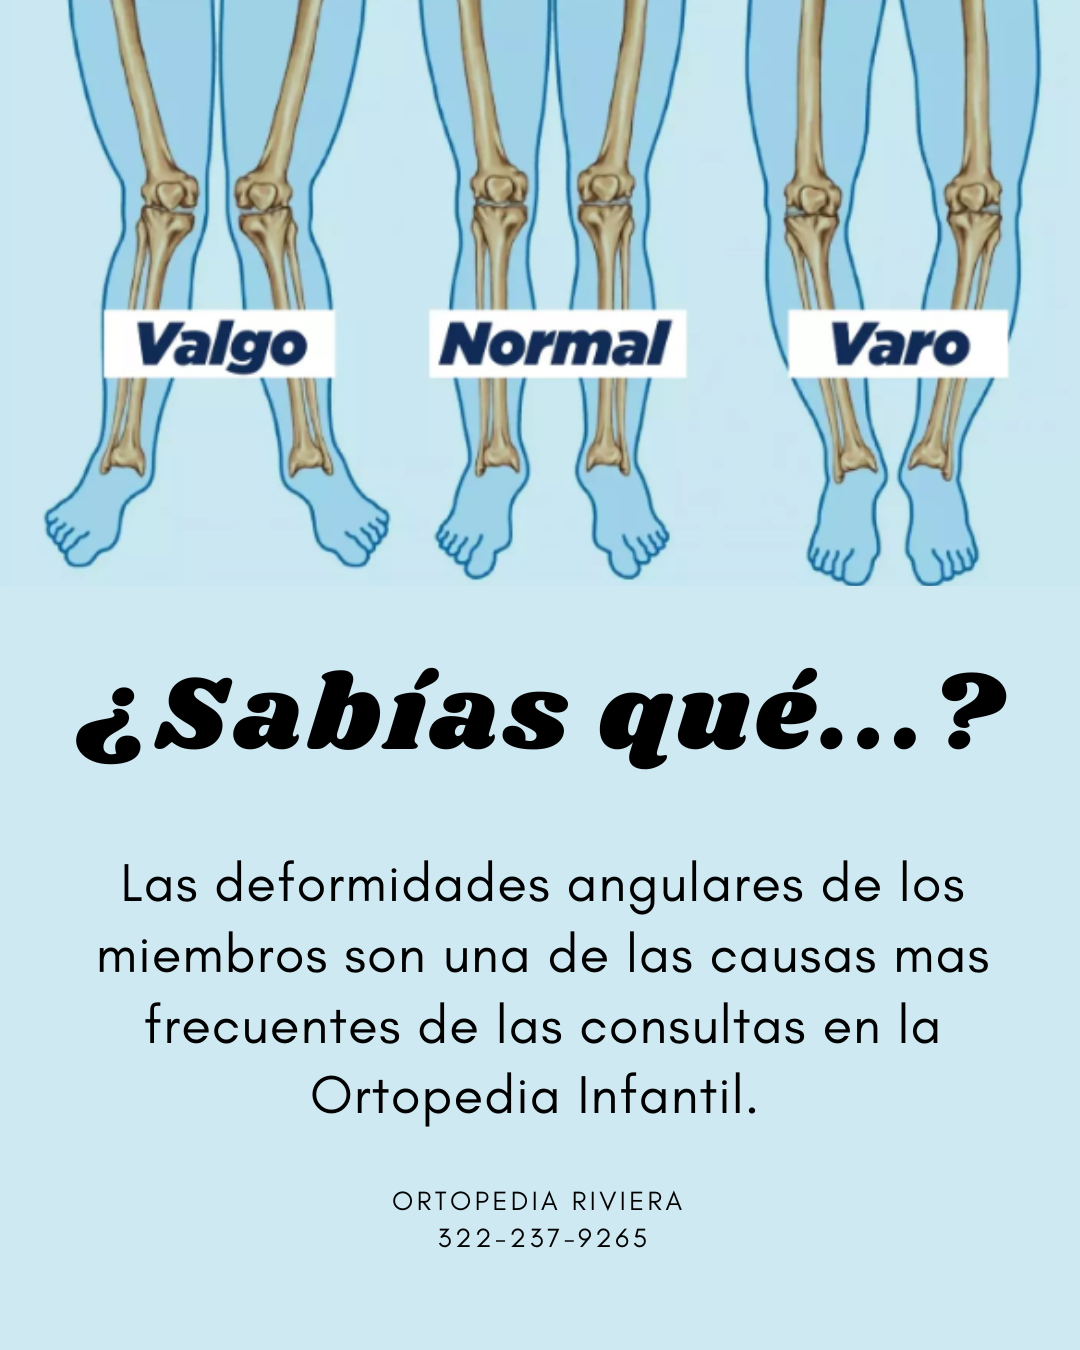

ORTOPEDIA INFANTIL